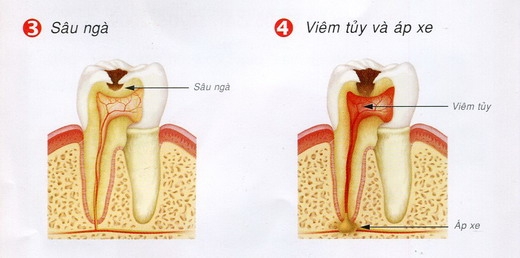

Sâu răng là tổn thương tạm thời xuất hiện trên bề mặt của răng. Tổn thương này hình...

Sâu răng là bệnh rất phổ biến, có thể gặp ở mọi lứa tuổi từ những trẻ răng...

Phục hồi thân răng sau điều trị

Răng chúng ta phía ngoài là men, bên trong là ngà, trong cùng là vùng mô mềm gọi...